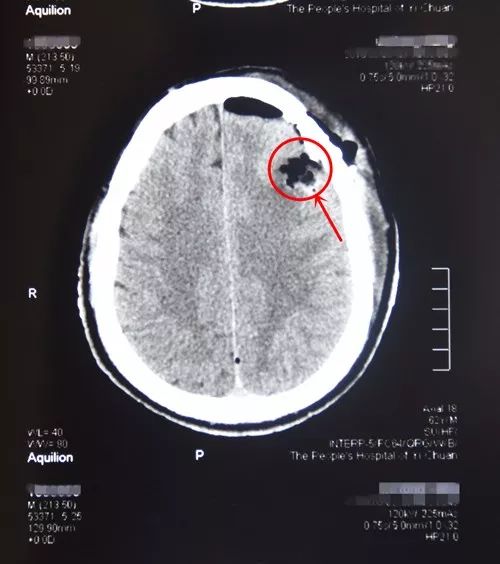

病人吴某,男,62 岁,因癫痫突然发作且呈癫痫持续状态,入住我院外二科。主管医生梁晓阳立即给予抗癫痫药物治疗,症状缓解后查MRI发现左额叶占位,考虑为海绵状血管瘤,经科室会诊后决定为吴某行左额叶占位切除术。在充分完善术前准备后,3月1日在全麻下采用左额叶弧形小切口,借助显微镜完整切除病灶,取出一直径约2.5cm的血管瘤。目前患者状况良好,神志清楚,正在进一步康复中。

术后CT显示:左额叶占位完整切除